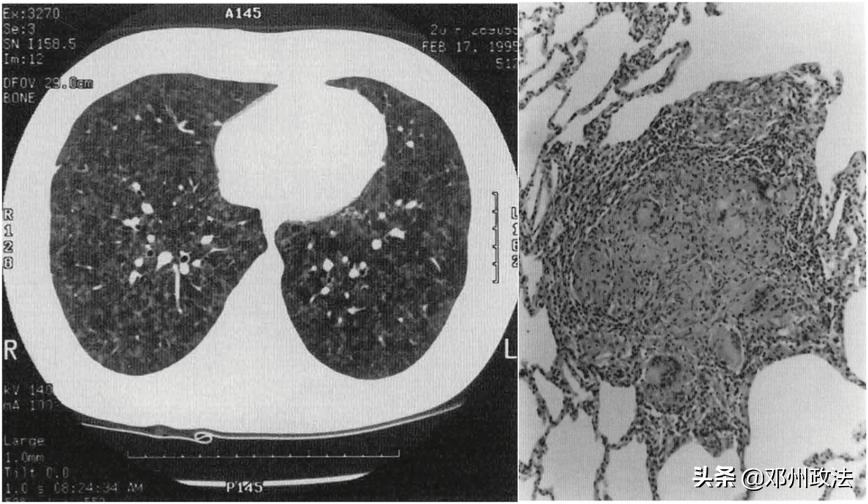

早在 1997 年,医学期刊 Chest 报道了一起相似的案例。 一位 20 岁的女患者在三年前开始出现咳嗽、喘不过来气等症状,但直到病情加重才来到医院就诊。经过检查,医生同样发现她存在肺弥散功能下降,CT 也显示有弥散的磨玻璃样病变。

左:高分辨率胸部 CT 提示基底节段呈磨玻璃样弥漫性浸润。右:HE 染色见远离细支气管的间质有多个非坏死性肉芽肿(图源:参考文献)

病理结果提示,患者肺中不规则地分布着许多小的非坏死性肉芽肿,从肉芽肿里,医生鉴定出六个耐酸杆菌,其中就包括鸟分枝杆菌复合群(MAC)。